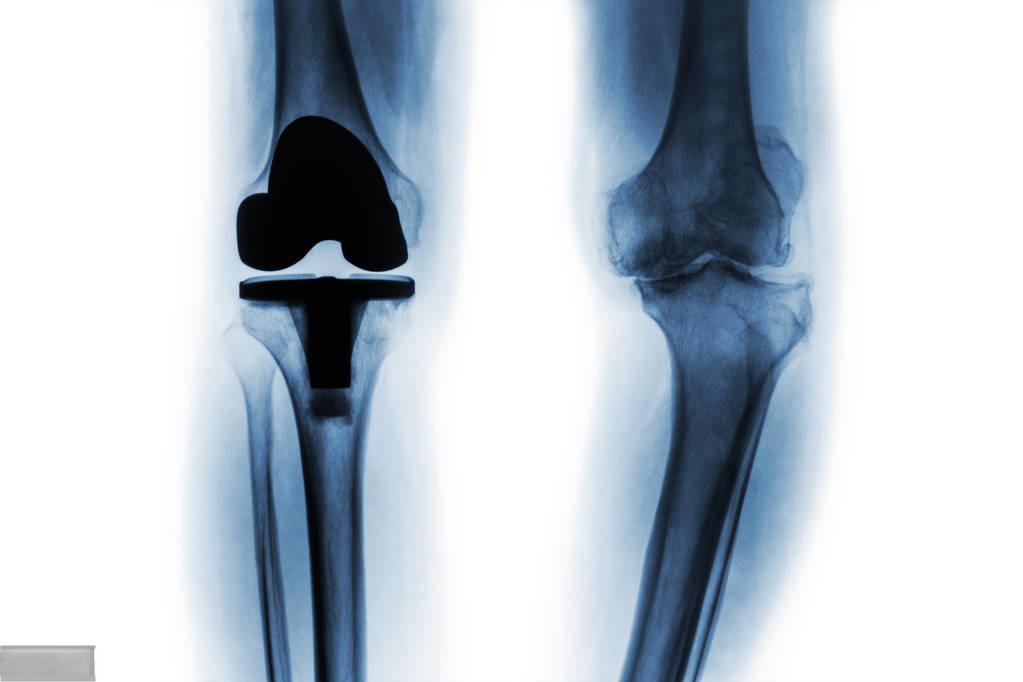

人工置换膝关节后遗症,医生提醒注意这4个并发症

人工置换膝关节手术已成为治疗严重膝关节疾病的有效方法。据统计,全国每年有数十万患者接受这一手术。然而,任何手术都存在风险,人工置换膝关节也不例外。医生提醒,术后需特别注意以下四种并发症:

第三是 假体松动 。随着时间推移,人工膝关节可能出现松动或磨损。这可能需要再次手术更换松动或磨损的部件。预防的关键在于科学运动,避免剧烈或对抗性运动,同时保持适度活动以增强关节周围肌肉。

人工置换膝关节手术虽然存在风险,但对许多患者来说仍是改善生活质量的重要选择。据统计,大多数膝关节置换预计至少持续15到20年。术后患者可以进行各种低冲击活动,如步行、游泳、打高尔夫球或骑自行车,但应避免高冲击活动。